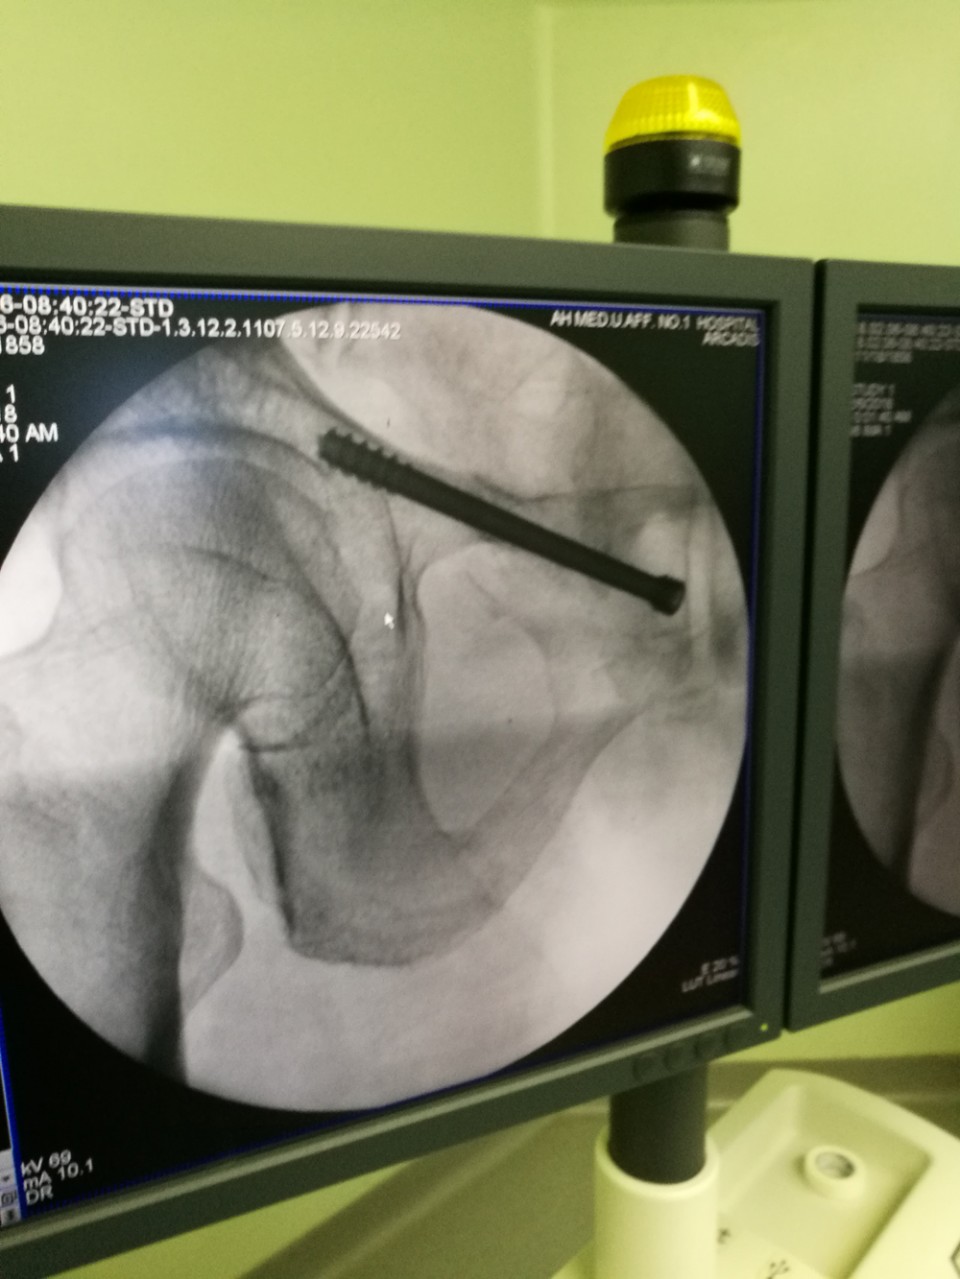

此次“天玑”骨科机器人被应用于两位骨折患者,首台是一位骨盆骨折患者,由于骨盆位置深,解剖关系复杂,传统手术需切开复位后钢板固定,创伤较大,手术时间长,容易出血,术后并发症多,而借助“天玑”机器人,可以闭合复位,并应用最新的闭合通道螺钉技术固定骨折,极大地减少了手术时间与手术创伤;对于另一位股骨颈骨折患者,有着“透视眼”、“稳定手”之称的“天玑”再次不负众望,利用计算机进行精确的置钉规划,使得螺钉分布更合理,固定更确切,更有利于骨折的愈合,从而减少股骨头坏死的发生率。

两台手术由创伤骨科七东科主任王刚,主治医师张琦与住院总医师章乐成共同完成,骨折复位后,影像扫描、数据传输到进钉点规划及螺钉置入的复杂过程,仅用半个小时,标志着我院创伤骨科水平在省内领先的基础上,进一步提升了在创伤救治能力上的优势。